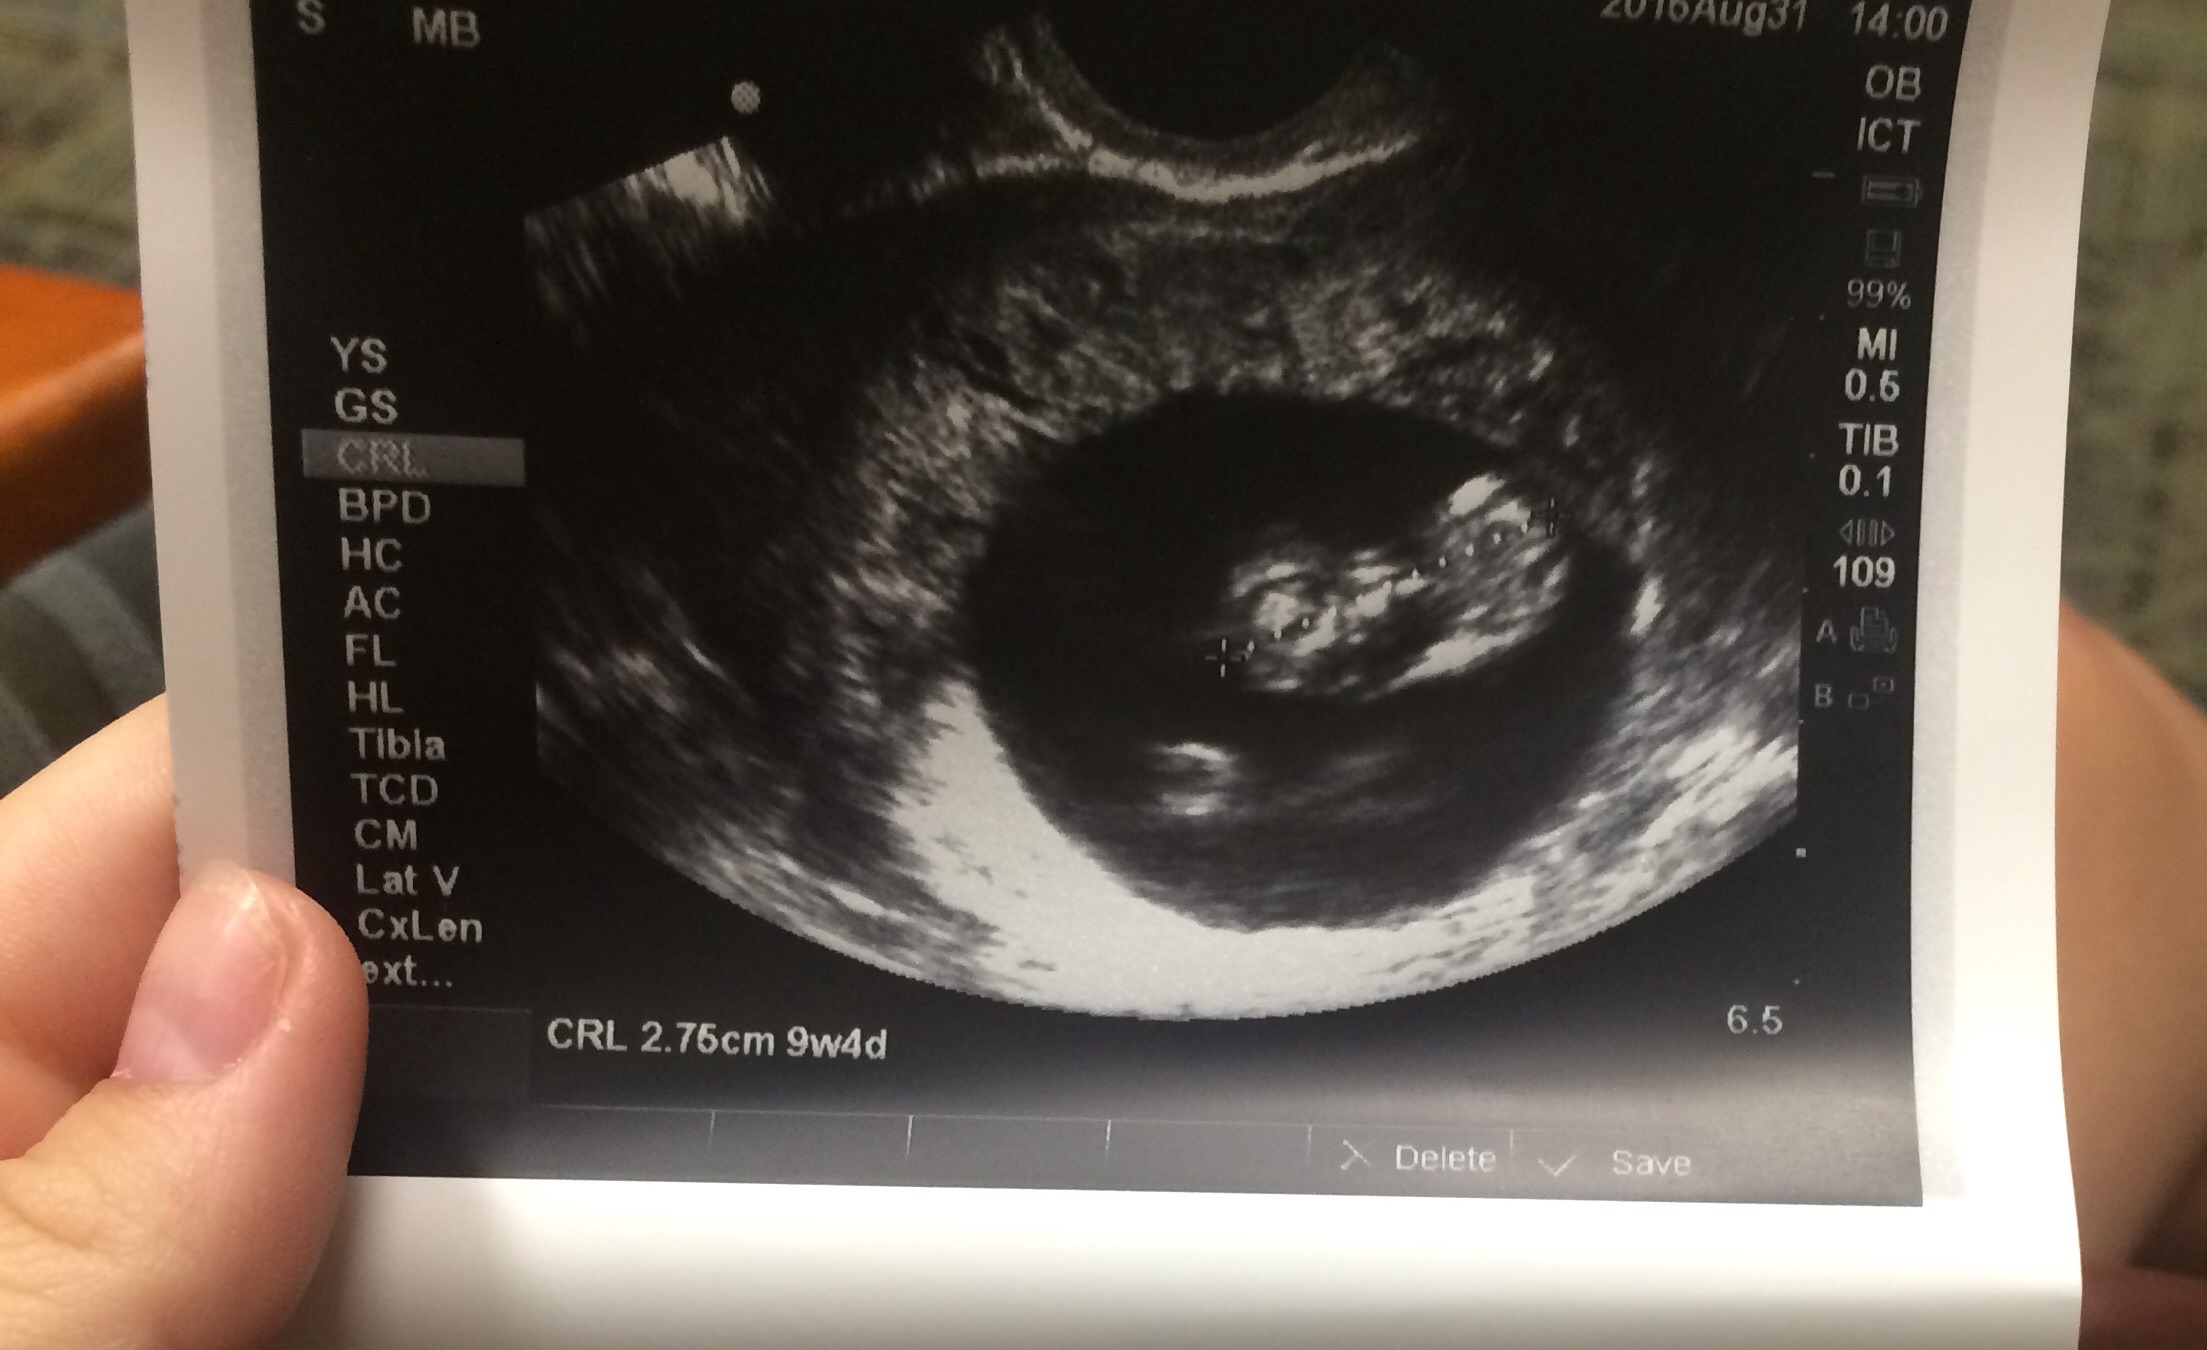

Had our first ultrasound today. Baby measured one day ahead, so exactly 9 weeks. My new edd is March 31st. Heart beat was 189 BPM. We got to see and hear its little heart beating!